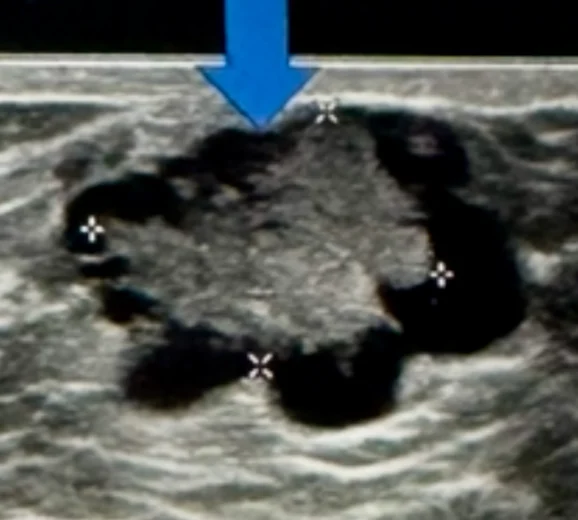

If something suspicious is found, medical imaging is used to investigate. Mammography, ultrasound, and sometimes MRI can distinguish between cancers and benign growths such as lipomas, haemangiomas, or fibroadenomas, but biopsy remains the definitive test.

There are four main types of breast cancer relevant to men. Ductal carcinoma in situ is confined to the ducts. Inflammatory breast cancer causes redness, swelling, and warmth of the breast. Invasive ductal carcinoma, which appears as a firm, painless lump, is the most common type in men. Paget’s disease of the nipple begins in the ducts beneath the nipple and presents with swelling and discolouration.